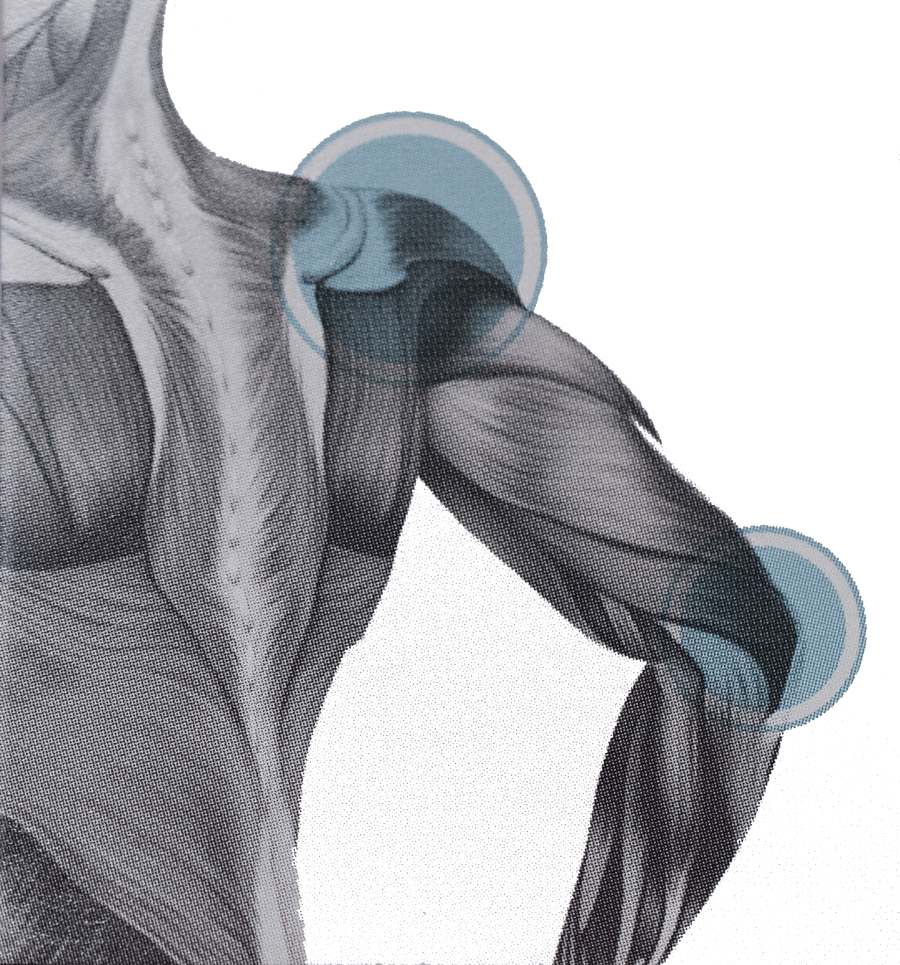

Integrative Neurosomatic Therapy is a structurally integrative approach to pain relief. It’s a way to analyze and thoroughly explore the muscles, tendons, and ligaments in order to find hidden sources of pain.

My goal is to help clients eliminate pain and to educate them on ways to prevent reoccurring injuries. When proper structure is restored to the body, the accompanying problems are often alleviated.